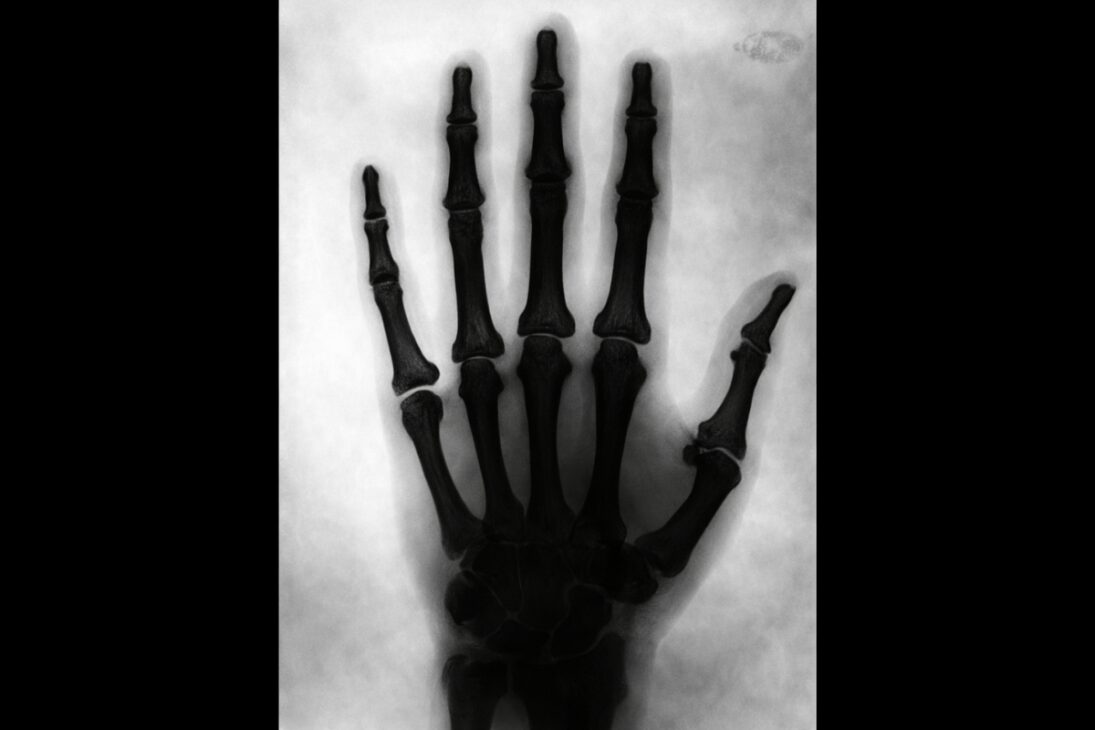

Nikola Tesla fez algo que ainda hoje impressiona quando o assunto é tecnologia e ciência. Em 1896, ele já estava produzindo imagens radiográficas do próprio pé e da própria mão, poucos meses depois do anúncio oficial da descoberta dos raios X por Wilhelm Conrad Röntgen, em novembro de 1895.

Tesla utilizou bobinas de alta tensão e tubos de descarga a vácuo desenvolvidos por ele para gerar as imagens. O resultado foi a produção de radiografias do próprio pé e da própria mão ainda em 1896.

Enquanto o termo raio X se popularizava rapidamente na imprensa internacional entre 1896 e 1897, Tesla preferia chamar essas imagens de shadowgraphs, reforçando um vocabulário próprio para um fenômeno que ainda estava sendo entendido.